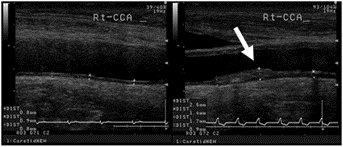

高血圧、糖尿病、高コレステロール血症は自覚症状に乏しいのですが放置しておくと心筋梗塞、脳卒中を引き起こす怖い病気です 学会の基準にのっとってしっかり管理いたします 定期的に動脈硬化検診いたします 頸動脈エコー、眼底検査、血管年齢